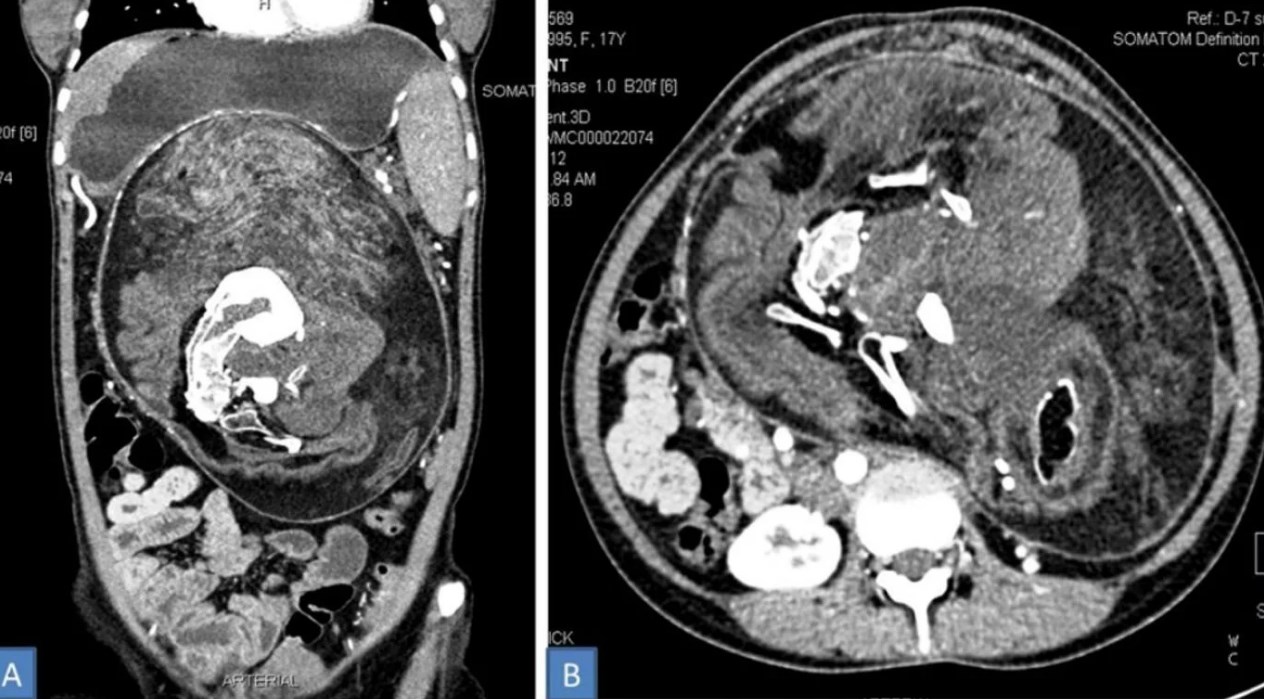

Tras varios estudios, que incluyeron una tomografía computarizada con contraste, los médicos lograron diagnosticar un caso de “Fetus in fetu”, por lo que decidieron extraer al “intruso” mediante una intervención quirúrgica.